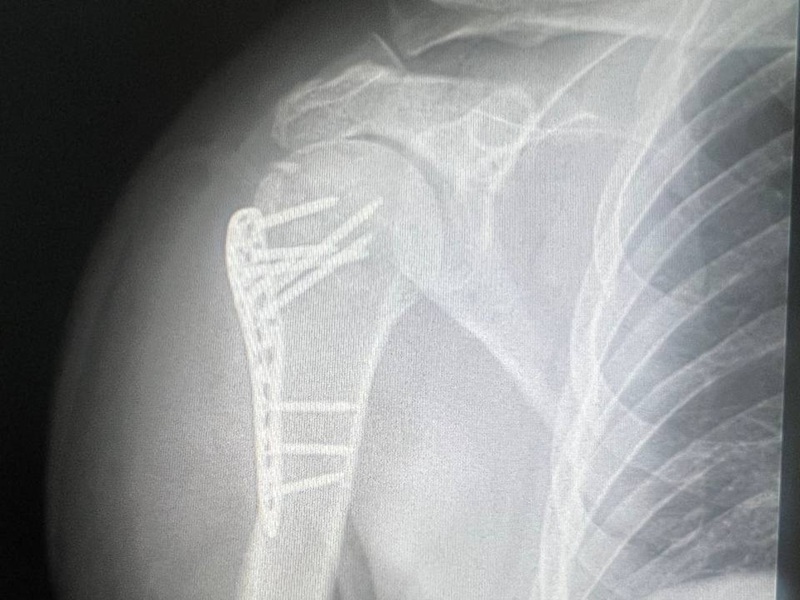

- наявність сторонніх тіл або післяопераційних змін (наприклад, ендопротезів).

- Знімок суглоба. Рентген-апарат фіксує зображення у цифровому або плівковому форматі. Лікар може зробити рентген суглобів в одній або кількох проекціях (фронтальна, бокова, коса) — залежно від поставленого діагностичного завдання.

Найчастіше обстежують колінні, кульшові, плечові, ліктьові, гомілковостопні суглоби, а також суглоби кисті. Це пов’язано з частотою травм і навантаженням на ці зони. Також проводять рентген для контролю стану після протезування або при артрозі.